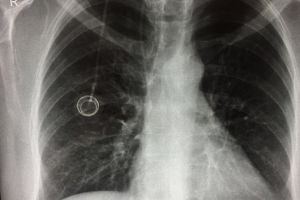

Salvaţi Copiii a donat Maternităţii Braşov un aparat radiologic pentru nou-născuţi

Prematuritatea rămâne una dintre principalele cauze ale mortalităţii infantile, a cărei rată plasează România pe primul loc din Uniunea Europeană. O statistică sumbră, pentru că datele oficiale arată că, într-o maternitate unde există aparatură medicală vitală, cei mai mulţi prematuri supravieţuiesc. Este motivul pentru care Organizaţia Salvaţi Copiii România continuă programul de dotare a maternităţilor din România şi